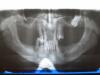

A3bykA Опубликовано 26 января, 2007 Поделиться Опубликовано 26 января, 2007 Ну вот, отказался я забирать эту поделку за 50 000,00. Забрал снимок - что посоветуете? Зубов кстати уже нет... ни одного! Ссылка на комментарий

Bier Опубликовано 26 января, 2007 Поделиться Опубликовано 26 января, 2007 Доктора, подскажите пожалуйста. Недавно консультировался у последнего доктора, внушает доверие. Он говорит что будем ставить по 4 импланта вверху и внизу. Причём все впереди. Спрашиваю - почему все впереди, ведь логично распределить нагрузку по челюсти. Он - чтобы не задеть нервы, которые идут сбоку. 1) Насколько обоснованно его опасение по поводу нервов? 2) Действительно ли передние импланты будут вполне надёжно работать на полных съёмных? 3) Если импланты все в куче, тогда может и по четыре не надо, по 2 вверху-внизу так же справятся? Вон и на фото вверху импланты распределены по челюсти. Азбукас, я Вам в личку отправил запросик, не откажите в любезности пообщаться! 1. надо снимок смотреть, но нерв проходящий в челюсти является нижней границей костной ткани для постановки имплантатов. Так что опасения скорее всего обоснованные. 2. да 3. да, есть такие наблюдения, что и двух в области клыков достаточно. снимок надо с собой, насчет вы у меня на следующей субботе в консультациях - это прям откровение какое-то..вы ничего не путаете? города например? А миниимпланты мы не ставим.... наверное автор в КДС записался и думает, что мы все от туда A3bykA если после удаления верхних зубов уже прошло 4 месяца - сделать новый снимок. Скорее всего хороший имплантолог сможет установить вам имплантаты и даже (есть такая методика "все на 4х") сделать несъемную конструкцию (это к хорошему имплантологу еще надо хорошего ортопеда и техника найти), хотя надо конечно и во рту смотреть. Ссылка на комментарий

Bier Опубликовано 27 января, 2007 Поделиться Опубликовано 27 января, 2007 я еще раз взглянул на снимок, наверху ситуация с костью после удаления не должна была измениться, внизу несколько могла. Через месяц повторный снимок, кстати если по толщине гребень приличный - внизу точно можно сделать несъемный протез. а на счет КДС - ну пошутил я Ссылка на комментарий

Bier Опубликовано 27 января, 2007 Поделиться Опубликовано 27 января, 2007 А скажите все обсуждения уважаемых стоматологов, по поводу моего ужастика, относятся только к нижней челюсти? С Верхней еще хуже чем я думал? Снимок такой же как и тот который я предоставил - только новый? Или какой то особенный? А у Вас в КДС (пошутил щас!), куда я записан разве нельзя сделать снимок? мы до этого обсуждали верхнюю челюсть, там основные проблемы. Ссылка на комментарий